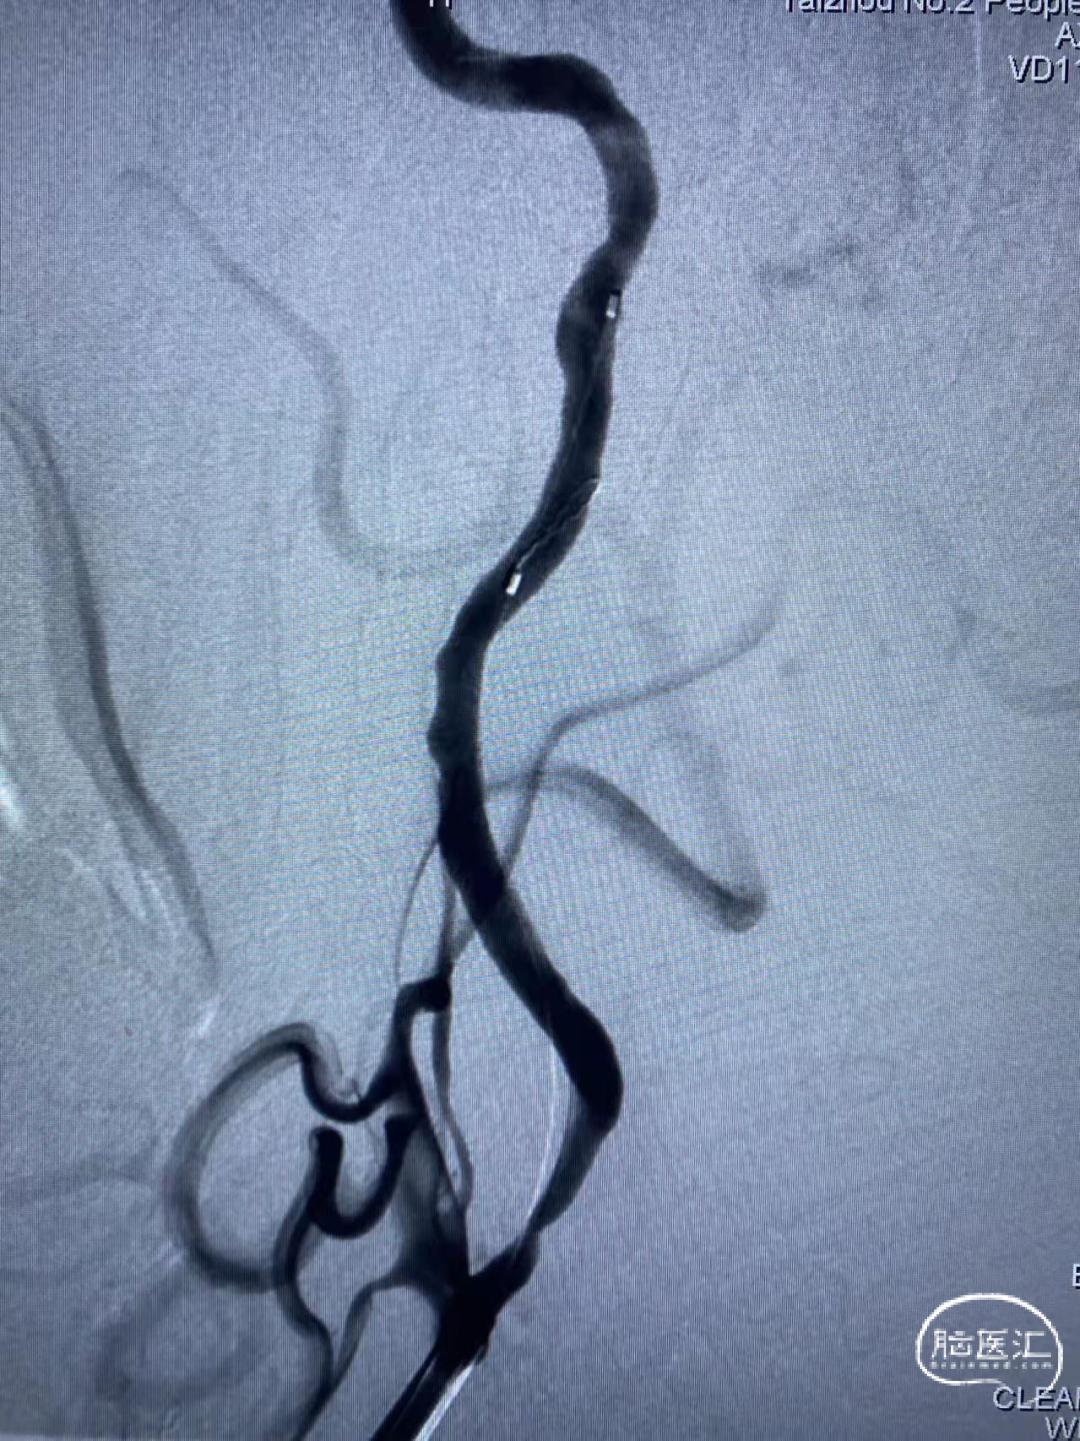

DSA检查:R-ICA窦部重度狭窄。

颅内段造影